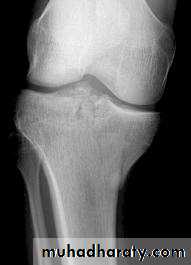

Tibial plateau fractures:Direct blow or fall from height may cause fracture of one tibial condyle or both.

Fracture lateral condyle is the commonest named as bumper fracture

caused by a force that abducts the tibia upon femur while the foot is fixed on ground.Patient usually is an adult, the knee joint is swollen, bruises, there is diffuse tenderness and doughy feel of haemarthrosis.

Imaging : X-ray

: anteroposterior, lateral & oblique views.

Tibial plateau fracture